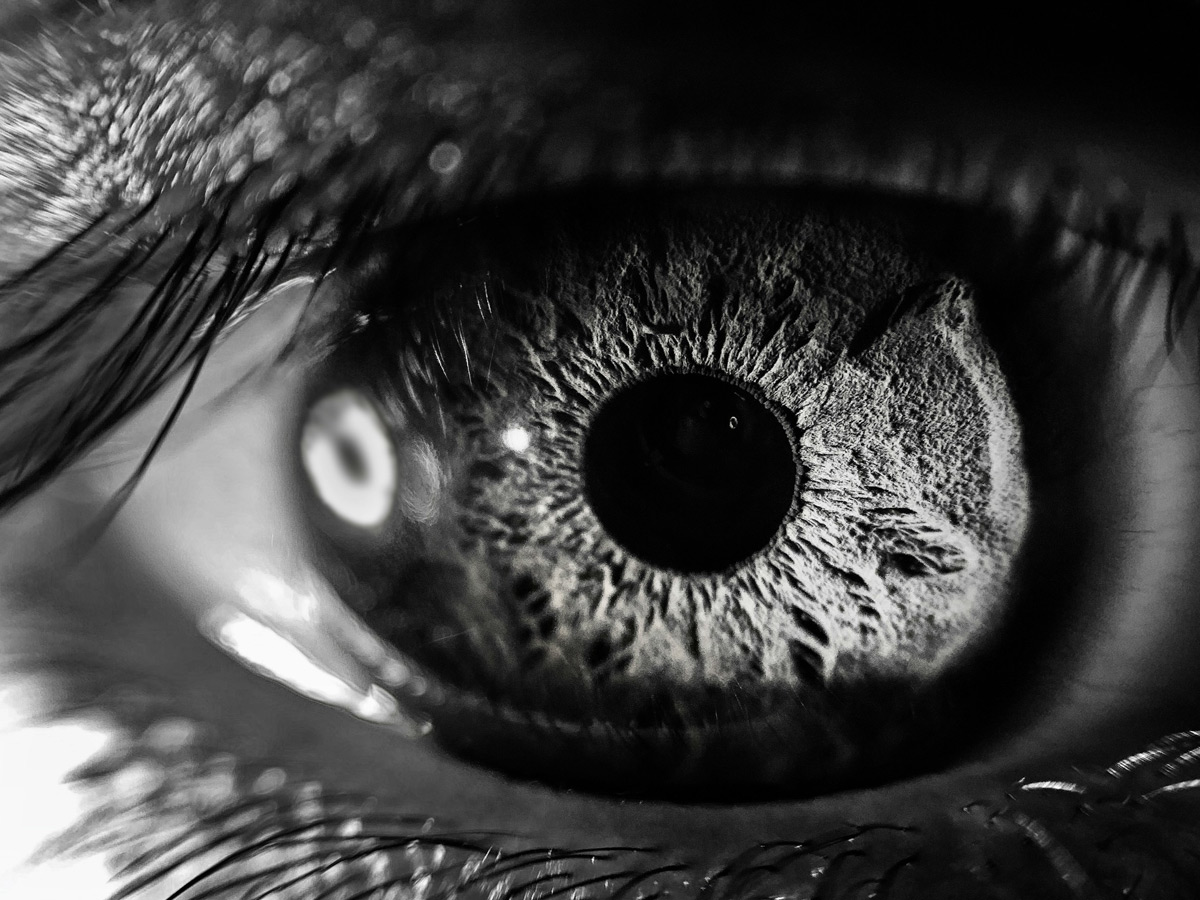

Virchu is the premier histopathology-powered precision oncology platform. Bringing clarity to the complexity of cancer and creating the conditions for world-changing discoveries.

AI is only as effective as the inputs on which it is trained— that's why we have developed a platform focused on training and validating world-changing oncology models. The Virchu platform provides users with access to highly-curated, de-identified, constantly evolving assets in a tool-agnostic computational environment. Our asset, infrastructure, and services are designed to unlock the insights that will transform cancer detection and care.

A purpose-built environment for curating, training, and validating AI to unlock new treatments, detections, and cures.